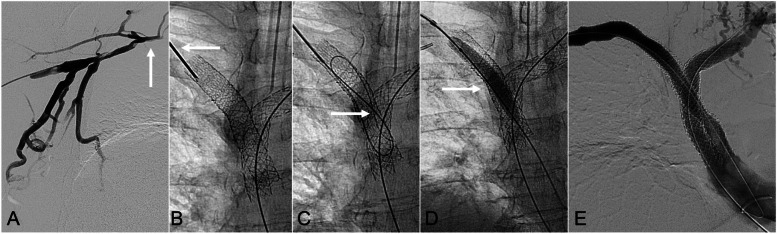

Direct percutaneous puncture of occluded venous stents as an adjunctive technique to restore patency.